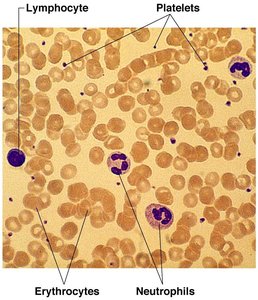

A blood smear under the microscope reveals the various formed elements, including erythrocytes, leukocytes (such as lymphocytes and neutrophils), and platelets. This visualization aids in the identification and study of blood cell morphology.

The formed elements of blood include erythrocytes, leukocytes, and platelets, each with distinct functions essential for homeostasis.

Formed Elements: Erythrocytes (RBCs), Leukocytes (WBCs), Platelets